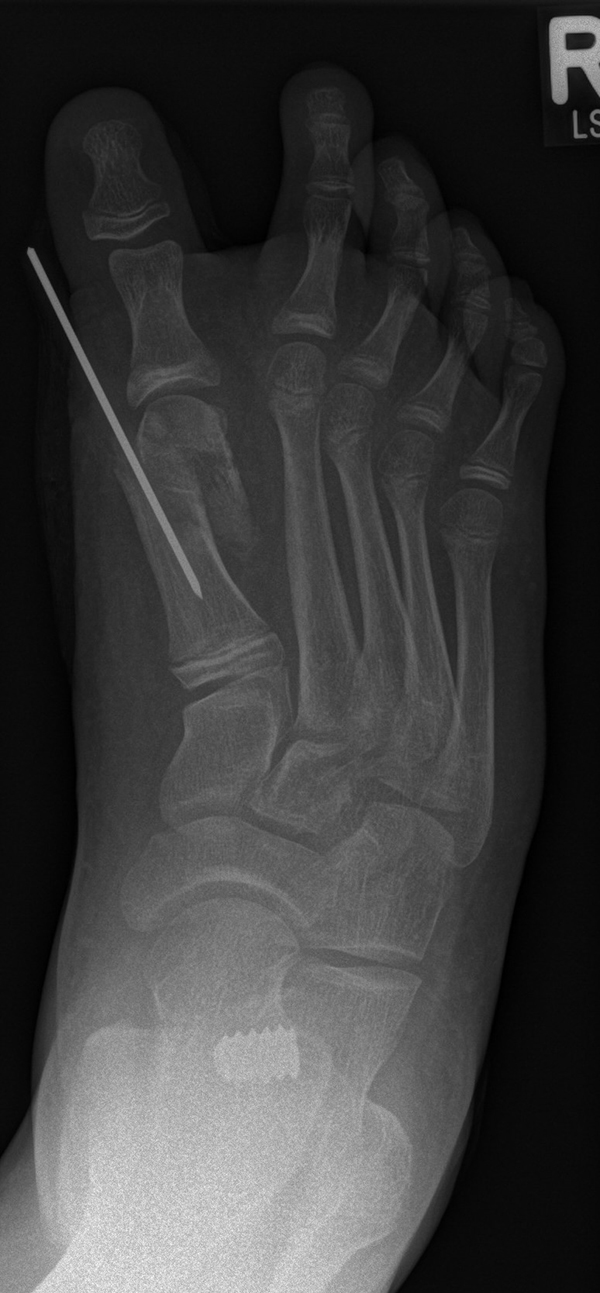

Calcaneus-Osteotomie

Die minimalinvasive Calcaneusverschiebeosteotomie bietet eindeutige Vorteile gegenüber dem offenen Verfahren, sodass wir bei Kindern und Jugendlichen nahezu keine offene Verschiebeosteotomie mehr durchführen. Am Calcaneus liegt die offene Wachstumsfuge dorsal. Bei der Durchführung müssen Schenkel der V-förmigen Osteotomie daher etwas steiler angelegt werden, in einem stumpfen Winkel (siehe Abb. 3 a-j). Für die Osteotomie liegen unsere Patienten auf dem Rücken und der BV wird für die exakte Seitaufnahme eingestellt. Der Fuß lagert auf einem hohen OP-Kissen und die Osteotomie kann bequem mit einem langen Kirschner-Draht und einem sterilen Stift angezeichnet werden (Abb. 15).

Abb. 15 a-b: Lagerung für die Calcaneus-Osteotomie minimalinvasiv.

Zum Lesen der Bildbeschreibung und zur Vollansicht bitte die Bilder anklicken. Bilder: A. Helmers.